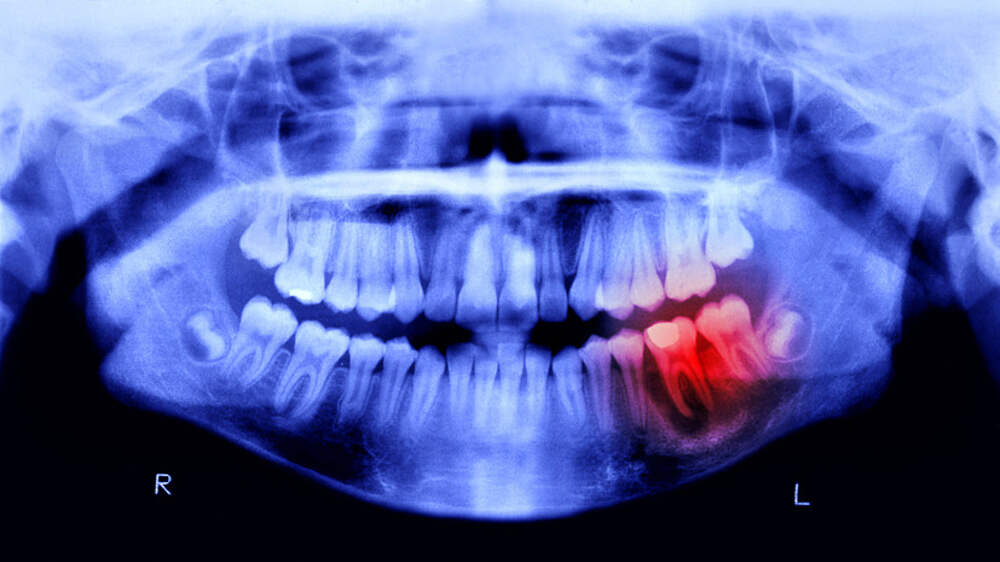

Основатель одной из федеральных сетей стоматологических клиник Залим Кудаев рассказал, что новое исследование южнокорейских учёных впервые выявило прямую связь между бактерией Streptococcus mutans, вызывающей кариес, и механизмами развития болезни Паркинсона. «Ранее исследования указывали на связь... Далее